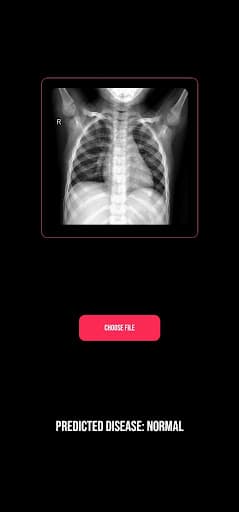

ProjectK is an AI-powered app that can detect pulmonary diseases by analyzing lung X-rays. I made it during a hackathon.

Screenshot 1 of ProjectKScreenshot 2 of ProjectKScreenshot 3 of ProjectKScreenshot 4 of ProjectKScreenshot 5 of ProjectKScreenshot 6 of ProjectK